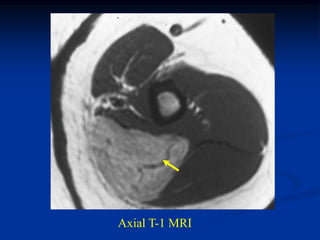

Case #1197

CLASSIC

37 year female with

hibernoma triceps m

Sagittal T-1 MRI

Axial T-1 MRI

Axial T-2 MRI

Axial gad

contrast MRI

Sagittal gad contrast

MRI

Surgical specimen showing tan color

Photomic

Hibernoma The hibernoma is a very rare lipoma variant seen usually in young adults in the intrascapular area of the back. It is painless and slow growing and ranges between 10 and 15 cm in diameter. Histolo- logically, the hibernoma demonstrates fine granular or vaculated cells consisting of brown fat and large amounts of glycogen. The treatment for this lesion is simple marginal resection with a very low potential for local recurrence.

Case #1197 CLASSIC 37 yearfemale with hibernoma triceps m Sagittal T-1 MRI